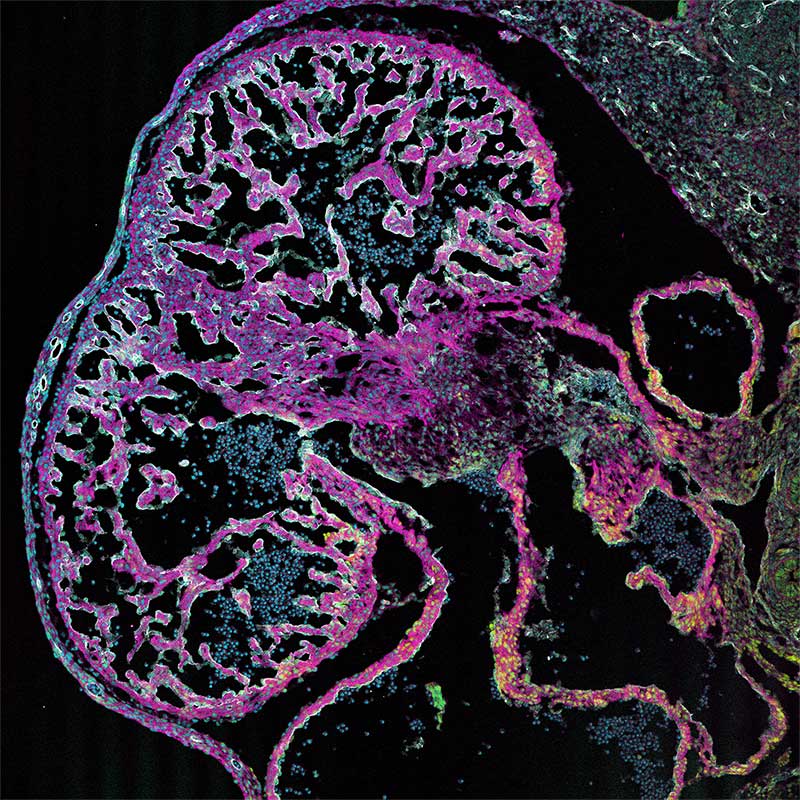

Lindsey (Avery) Fitzsimons '10, is a 5th year PhD student in Biomedical Science at the University of Maine, where she is currently working to complete her doctoral dissertation exploring the cellular disease processes involved in congenital heart disease/congenital heart defects. Lindsey began her tenure at Skidmore as a Studio Art/Art History major, but quickly became fascinated by the mysterious processes going on underneath the skin of the human body. Lindsey graduate from Skidmore with her B.S. in Health and Exercise Sciences, went on to complete a Master of Science degree in Clinical Exercise Physiology, and has spent the past 7 years working in various national and international biomedical research labs. Although she is committed to a career as a research scientist, Lindsey has continued to integrate her love for the visual arts through fluorescence microscopy, where she uses an experimental method called immunohistochemistry (immunofluorescence) to target specific proteins of interest by tagging them with specific fluorescent proteins (fluorophores) and imaging them using a specialized method of laser-microscopy , termed confocal microscopy (Leica Biosystems). Lindsey's images depict various stages of embryonic heart development (in mouse), and highlight different molecular targets critical to many of these developmental processes. IN addition to her research and teaching medical students at the University of New England College of Osteopathic Medicine (Biddeford, ME), Lindsey is passionate about communicating her science through her Instagram account (LAF_in_the_LAB), where she showcases many of her images to advocate for women, girls and moms in Science, Technology, Engineering, Art and Mathematics (STEM/STEAM).

The Developing Endocardium: (2D/10X) Confocal microscopy of the embryonic mouse heart (left ventricular wall) at embryonic timepoint E12.5

Immunohistochemical analysis using primary clonal antibodies and secondary fluorophores